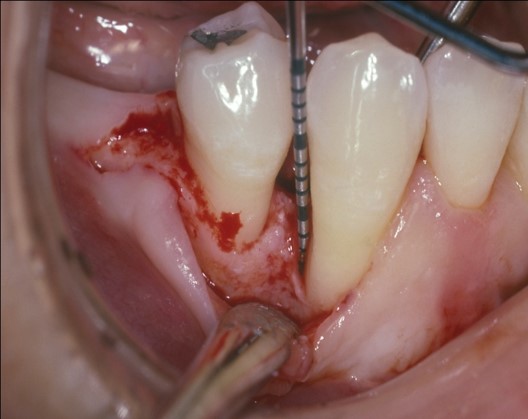

Fig 15. A tunneling procedure with a small connective tissue graft was performed to establish extra soft tissue with a thickened biotype.

Figure 15

However, by giving consideration to the most appropriate and minimally invasive sequence of care, this led to performing predictable procedures beginning with a tunneling procedure with a small connective tissue graft (Figure 15). Once the connective tissue graft healed (Figure 16), extra soft tissue with a thickened biotype was available. This would enable minimally invasive extraction using piezosurgery—without damaging the soft tissues (Figure 17)—followed by immediate implant placement according to 3D implant treatment planning (Figure 18 through Figure 20).